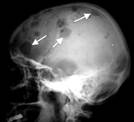

МИЕЛОМНАЯ БОЛЕЗНЬ - злокачественная опухоль костного мозга. Различают следующие разновидности: 1) множественно-очаговая; 2) диффузно-поротическая|; 3) остеосклеротическая|; 4) изолированная (солитарная|). Миелома разрушает костную ткань. Рентгенологически: выявляются|проявляются| множественные округлые дефекты, диаметром от нескольких миллиметров до нескольких сантиметров с резкой контурированностью| каждого отдельного дефекта (пробойниковые дефекты). Реактивных изменений|смен| со стороны соседних тканей не бывает.

Рис..31. Миеломная болезнь.